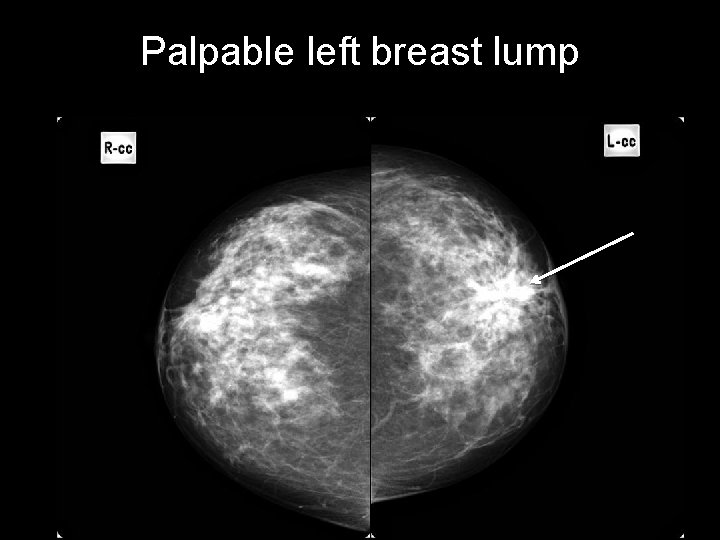

Palpable left breast lump CASE 3 • Left breast lump • Age: 45 years old • Gender: Female • First study? – Ultrasound – Mammography – MRI w contrast

Palpable left breast lump architectural distortion area of architectural distortion with pleomorphic calcifications microcalcifications

Palpable left breast lump a region of architectural distortion and pleomorphic calcification BREAST CARCINOMA http: //radiopaedia. org/cases/breast-carcinoma